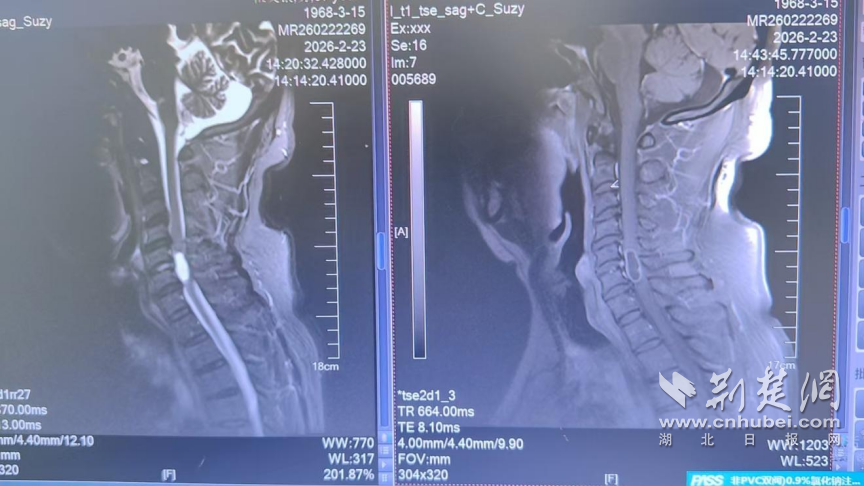

患者的影像报告。 通讯员 供图

入院后,脊柱外科团队高度重视,迅速为其完善相关检查。结合患者体征及影像学表现,团队高度怀疑颈椎椎管内肿物(椎管内肿物是神经系统的严重疾病,早期精准诊断与规范治疗至关重要)。体格检查显示患者颈部活动受限,结合椎间孔挤压试验、臂丛牵拉试验等,进一步印证了脊髓受压的诊断。